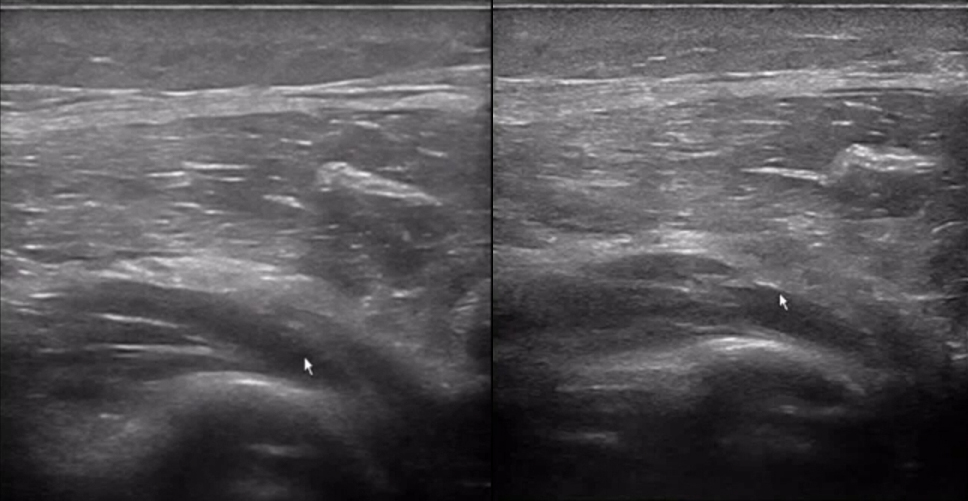

The patient experienced significant pain during wrist extension, indicative of "wrist drop."

Ultrasound revealed a "sandglass" or "sausage-like" change in the radial nerve, confirming nerve compression.

Such detailed imaging results are often critical for diagnosing and managing conditions like wrist drop, making POCUS (Point-of-Care Ultrasound) an invaluable tool in clinical practice.